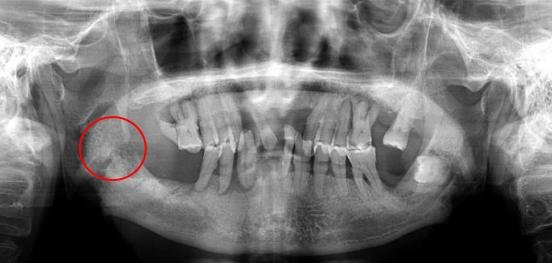

口腔科吴艳妮医师诊查中发现李爷爷右侧上下眼睑、眶下及右下面部肿胀明显,伴有压痛、张口中度受限、口内右下6、7缺损、未见右下8。右侧颊侧粘膜肿胀明显。CBCT示:右下8埋伏阻生,右下8根尖上方可见2.0*2.0cm的圆形低密度影。诊断为颌骨囊肿,需手术治疗。

考虑到李爷爷已年逾80,且在急性感染期,为其控制感染后,进行了右下8埋伏牙拔除术、颌骨囊肿摘除术,术后病检示“颌骨根尖囊肿”。

术后